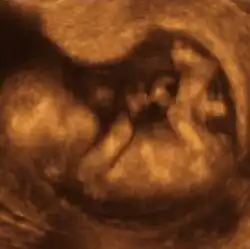

- Ultrassonografia

A ultrassonografia médica, também conhecida como ecografia, usa ondas sonoras de alta frequência para criar imagens do interior do corpo. A máquina de ultrassom envia ondas sonoras para o corpo e é capaz de converter os ecos de som de retorno em uma imagem. A tecnologia de ultrassom também pode produzir sons audíveis de fluxo sanguíneo, permitindo que os profissionais médicos usem sons e imagens para avaliar a saúde do paciente. O ultrassom é frequentemente utilizado para avaliar:

- Gravidez;

- Anormalidades no coração e vasos sanguíneos;

- Órgãos na pelve e no abdômen;

- Sintomas de dor, inchaço e infecção.